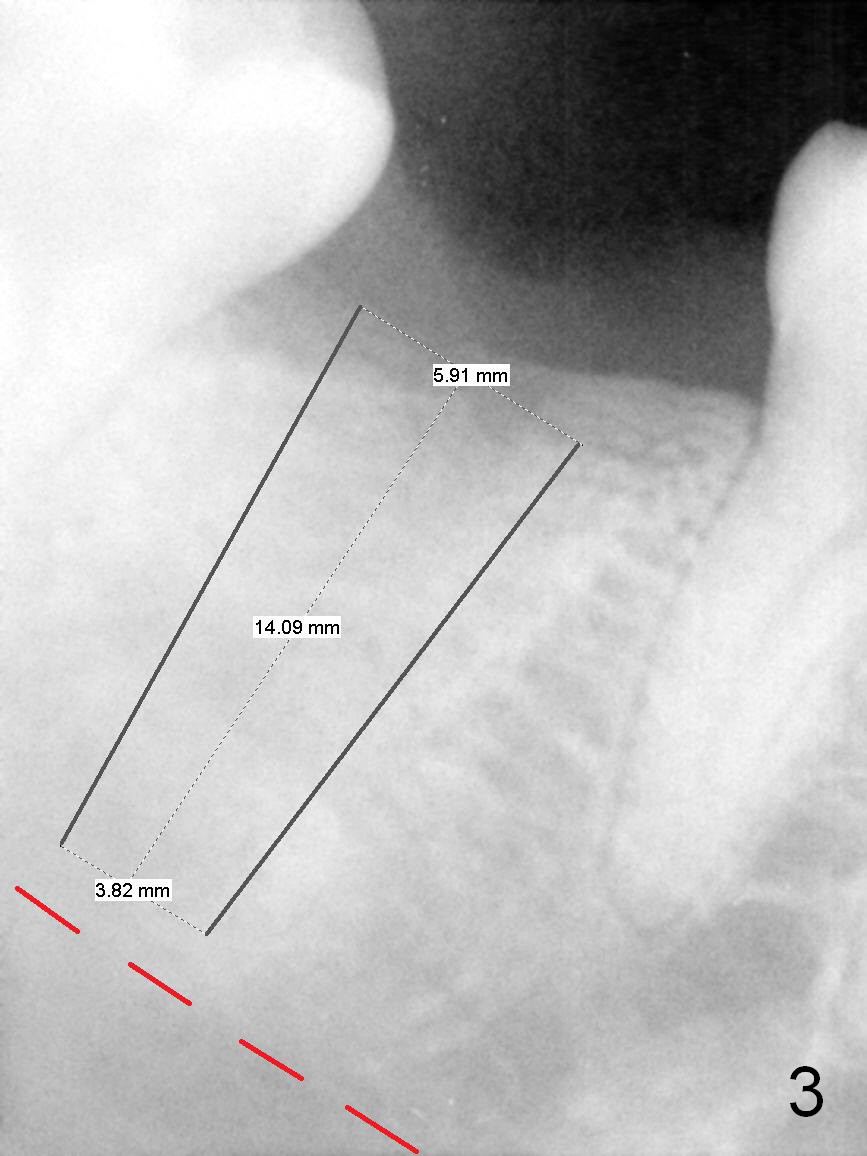

PA in Fig.2 is taken 2 months post extraction, while Fig.3 shows design of a 5.9x14 mm bone-level implant. It appears that the implant is a little too long (red dashed line: the superior border of the Inferior Alveolar Canal). Initial osteotomy depth will be 12 mm. In fact the implant was designed to be supracrestal distal (mistake, even if bone graft is well executed). An incision will be made for visibility.